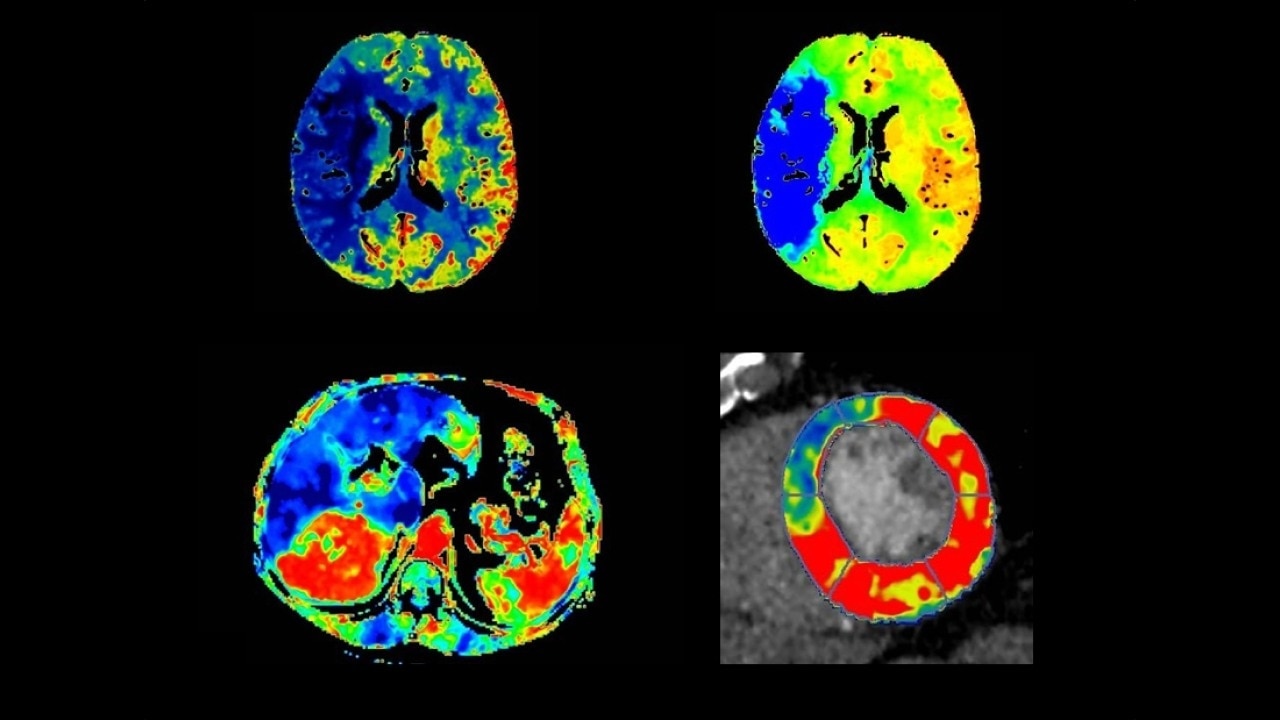

Body perfusion

Optimized protocols for kidney, soft tissue, liver perfusion and other body tumors

Myocardial perfusion

Complete guided workflow for assessing dynamic CT myocardial perfusion